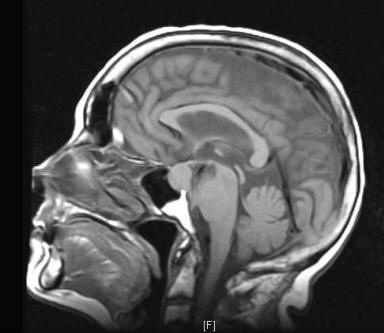

Undiagnosed Brain Tumor Pictures

Photos of Undiagnosed Brain Tumor

Images of Undiagnosed Brain Tumor

Undiagnosed Brain Tumor Photos

Pictures of Undiagnosed Brain Tumor

Undiagnosed Brain Tumor Images